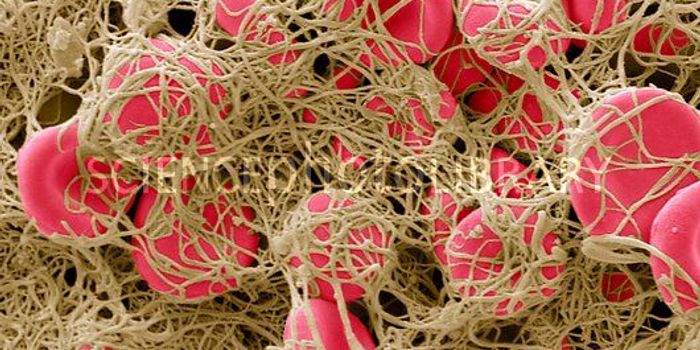

DEC 12, 2013MicrobiologyThe phrase "blood clot" rarely has a positive spin-most people associate blood clots with traumatic and potentially fata ...

NOV 09, 2017CardiologyBlood clots are normally seen as something to be avoided, something with dangerous consequences such as heart attack, st ...

SEP 17, 2020Clinical & Molecular DXBlood clotting, also known as coagulation, is a critical biological mechanism to prevent excessive blood loss in the eve ...

FEB 24, 2015CardiologyResearchers at the UNC School of Medicine have found that the blood platelet protein Rasa3 is critical to the success of ...

MAY 25, 2017CardiologyThe development of a blood clot could be very beneficial or very dangerous, depending on the situation. On one ha ...